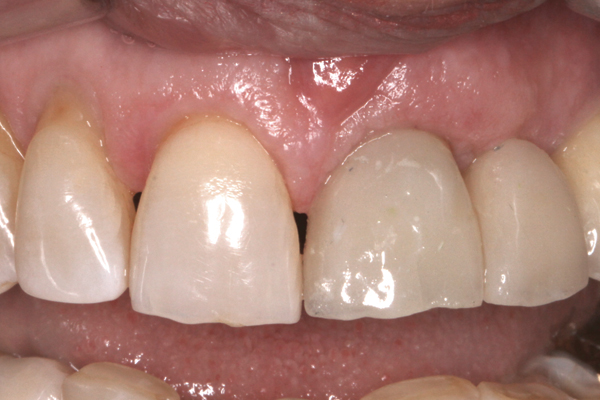

Fig 3. Placement of abutments that create blanching of the peri-implant soft tissue will result in unpredictable remodeling of the tissue to a more apical position, which may create an esthetically displeasing result. This is best managed in the esthetic zone by shaping the soft tissue in the provisional stage rather than with the definitive abutment.

Figure 3